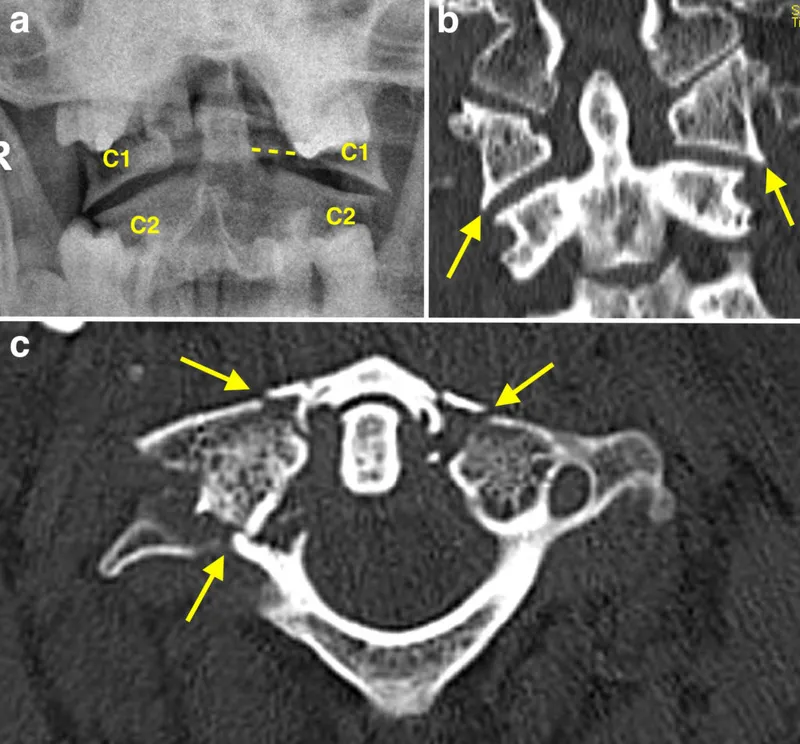

⭐ Jefferson fracture (C1 burst fracture) results from axial loading; assess transverse ligament integrity using "Rule of Spence" on open-mouth odontoid view.

- Cervical Fractures: Jefferson (C1 burst), Hangman's (C2 bilateral pedicle #), Odontoid (Type II unstable).

- X-ray: First line for trauma, alignment. Views: AP, Lateral, Odontoid.

- CT: Superior for bone detail, complex fractures.